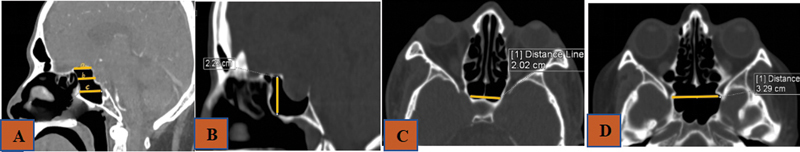

引言 内窥镜经蝶手术(ETS)是垂体手术的标准做法。在 ETS 中,蝶鞍暴露是决定残留疾病的主要因素。关于蝶鞍解剖变异对术中蝶鞍暴露影响的研究文献并不多。目的 本研究旨在确定蝶窦变异是否对蝶窦暴露和残余肿瘤体积有影响。方法 这是一项前瞻性研究,于 2020 年 6 月至 2022 年 6 月期间在印度南部的一家三级医疗中心进行,共有 21 名计划接受 ETS 的研究参与者。评估术前计算机断层扫描(CT)和磁共振成像(MRI)参数与术中蝶窦暴露面积和残余肿瘤体积的关系。结果 蝶窦尺寸,如蝶窦前宽(平均 = 1.89 ± 0.51 厘米)、最大宽度(平均 = 2.94 ± 1.09 厘米)、蝶窦前深(平均 = 1.14 ± 0.55 厘米)、蝶窦上深(平均 = 1.08 ± 0.24 cm)、髌下深度(平均 = 2.36 ± 0.92 cm)、髌前高度(平均 = 2.22 ± 0.47 cm)或 9 个颈内动脉(ICA)相关测量值与术中平均蝶鞍暴露面积(0.57 ± 0.28 cm 2)没有任何相关性。此外,蝶鞍暴露是否充分与残余肿瘤也没有关系。与无残留肿瘤的患者(5.9 [6.8-5.2] cm 3)相比,有残留肿瘤的患者术前肿瘤体积更高(20.2 [55.3-13.2] cm 3)。肿瘤的扩展与残留肿瘤体积有显著关系。结论 根据本研究,蝶窦的解剖变异不会影响蝶窦暴露的充分性。关于残余肿瘤体积以及术前肿瘤体积和扩展情况,还需要进一步研究。

Introduction  Endoscopic transsphenoidal surgery (ETS) is the standard practice in pituitary surgeries. The sellar exposure becomes the main factor which determines the residual disease in ETS. Not many studies can be found in the literature on the influence of anatomical variations of the sphenoid on intraoperative sella exposure. Objective  The aim of the current study is to ascertain whether sphenoid sinus variations play a role in sellar exposure and residual tumor volume. Methods  This is a prospective study conducted in a south Indian tertiary care center between June 2020 to June 2022, with 21 study participants who were scheduled to have ETS. The relation of preoperative computed tomography (CT) and magnetic resonance imaging (MRI) parameters with the intraoperative area of sellar exposure and residual tumor volume was evaluated. Results  Sphenoid sinus dimensions, like presellar width (mean = 1.89 ± 0.51 cm), maximum width (mean = 2.94 ± 1.09 cm), presellar depth (mean = 1.14 ± 0.55 cm), suprasellar depth (mean = 1.08 ± 0.24 cm), infrasellar depth (mean = 2.36 ± 0.92 cm), presellar height (mean = 2.22 ± 0.47 cm), or the 9 internal carotid artery (ICA)-related measures, did not have any correlation with the mean intraoperative area of sellar exposure (0.57 ± 0.28 cm 2 ). Also, the adequacy of sellar exposure did not relate to the residual tumor. Preoperative tumor volume was found to be higher (20.2 [55.3-13.2] cm 3 ) in patients with residual tumor compared with those with no residual tumor (5.9 [6.8-5.2] cm 3 ). Tumor extension had a significant association with the residual tumor volume. Conclusion  According to the present study, anatomical variations of the sphenoid sinus do not influence the adequacy of sellar exposure. Further studies need to be undertaken concerning residual tumor volume as well as preoperative tumor volume and extension.